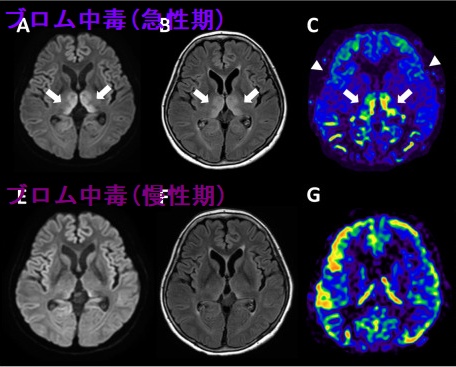

市販の解熱鎮痛薬には、ブロム中毒 (Bromism) の原因となるブロモバレリル尿素を含むものがあります。短期間の使用なら問題ありませんが、長期間服薬するとブロム中毒に至る可能性があります。さらに、ブロモバレリル尿素には依存性があるため、服薬せずにいられなくなる依存症を来す危険があります。

慢性ブロム中毒の症状は、

- 不可逆的な神経障害;小脳失調(回転性めまい、運動失調)、聴力障害、構音障害、錐体外路症状、精神障害(不安・易怒性混乱・幻覚・虚脱、昏迷)、意識障害(見当識障害・昏睡)(甲状腺クリーゼ・ 粘液水腫性昏睡 ・橋本脳症の様)

- 食欲不振、便秘(甲状腺機能低下症の様)

- チェリー血管腫やざ瘡様皮疹、紅斑

- 偽性高クロール血症;臭素(Br:ブロム)イオンを同じハロゲン元素の塩素(Cl:クロール)と間違えて検出するため

[Toxicol Mech Methods. 2025 Jun 24:1-26.][Am J Emerg Med. 2022 Oct;60:229.e5-229.e6.][Am J Emerg Med. 2020 Aug;38(8):1696.e1.]